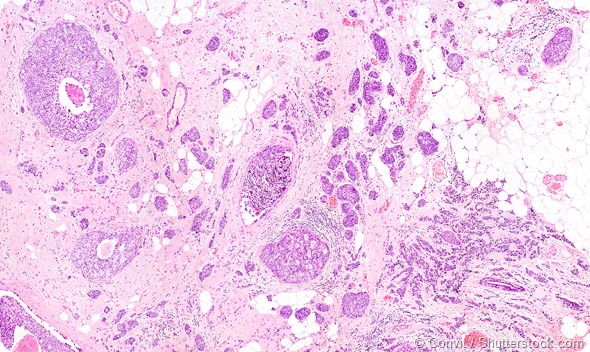

Tumor cells under microscope labeled with fluorescent molecules